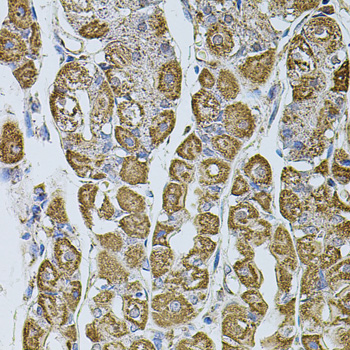

Immunohistochemistry of paraffin-embedded rat brain using UQCRC1 at dilution of 1:100 (40x lens).

Immunohistochemistry of paraffin-embedded human prostate using UQCRC1 at dilution of 1:100 (40x lens).

Immunohistochemistry of paraffin-embedded human stomach using UQCRC1 at dilution of 1:100 (40x lens).

应用详情:WB 1:500 - 1:2000

IHC 1:50 - 1:200